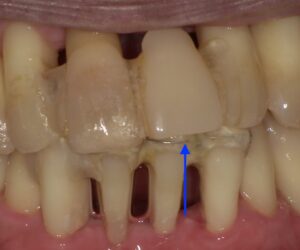

画像の矢印の歯が歯周病が進行し暫間固定で経過を見ていました。

周囲のホ根が完全になくなってしまいましたので

抜歯をし、その歯を接着剤でとめました。

矢印がその歯になります。